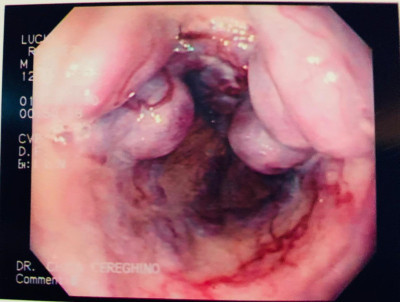

Paciente con várices esofágicas